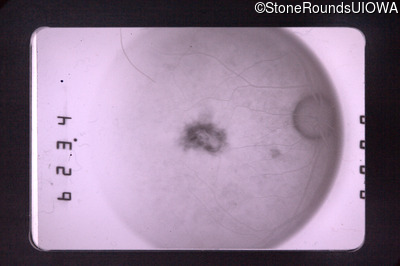

Fluorescein Angiography - Right - 20/50 +1

Exemplar